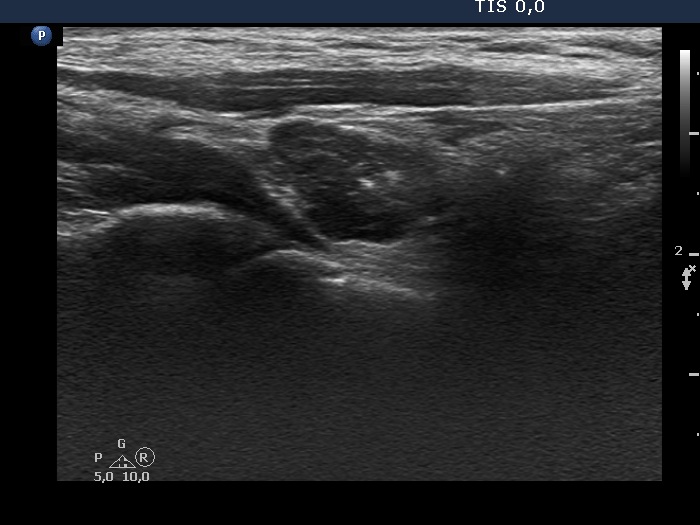

Ultrasound. Connective tissue replaced the thyroid parenchyma in both thyroid beds. There was a hypoechoic mass in the lower part of the right thyroid bed dorsal to the carotid artery. The lesion was a mixed, dominantly solid nodule and had microcalcifications.

Aspiration cytology from the hyperechogenic lesion resulted in papillary cancer. Wash-out thyroglobulin was 6905 ng/mL